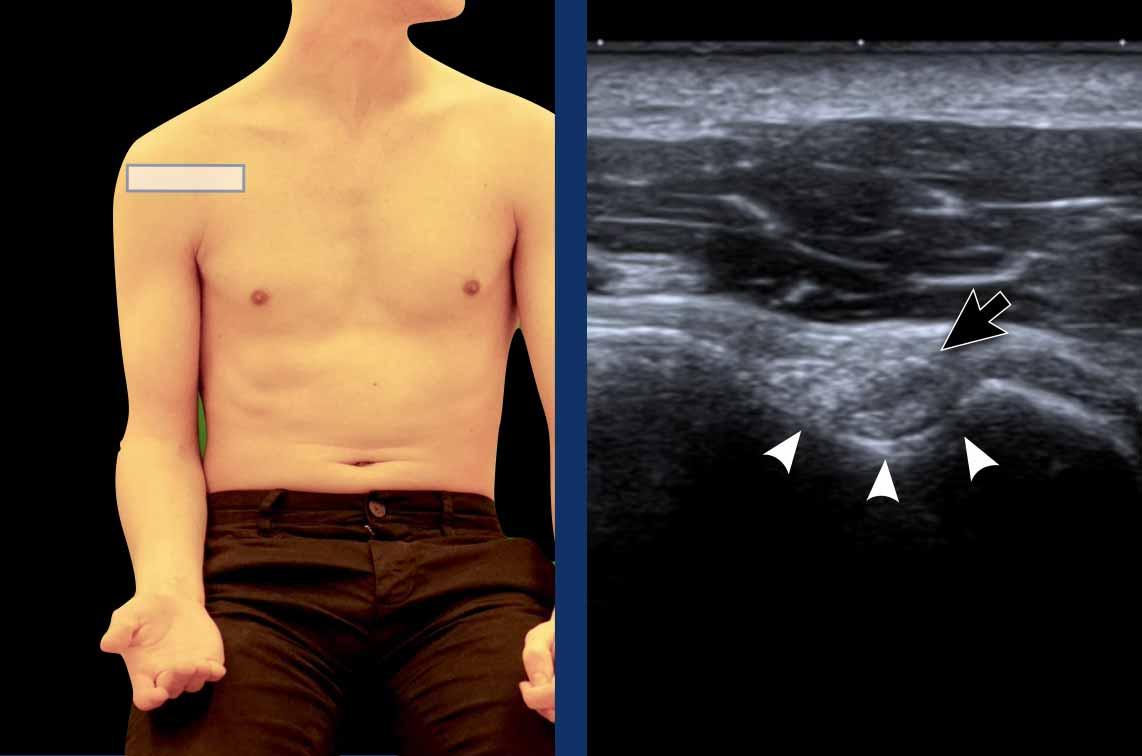

Cẳng tay bệnh nhân nên được ngửa và xoay trong nhẹ về phía gối đối bên.

Ở tư thế này, gân cơ nhị đầu dài (LHB) xuất hiện như một cấu trúc tròn với cấu trúc âm dạng sợi (mũi tên đen) nằm trong rãnh gian củ (đầu mũi tên trắng).

Tính dị hướng

Tính dị hướng là một artefact xảy ra khi chùm tia siêu âm không vuông góc với gân cơ nhị đầu dài (LHB). Sự lệch trục này dẫn đến giảm phản xạ sóng âm, gây mất độ phân giải và làm cho cấu trúc có hình ảnh tối, giảm âm (mũi tên đen). Trong một số trường hợp, điều này có thể tạo ra ấn tượng rằng gân LHB bị trật ra khỏi rãnh liên củ.

Để khắc phục hiện tượng dị hướng, hãy điều chỉnh lại vị trí đầu dò sao cho chùm siêu âm vuông góc với gân. Khi đó, gân cơ nhị đầu dài (LHB) sẽ lấy lại hình ảnh đặc trưng tăng âm, dạng sợi (mũi tên trắng).

Cần lưu ý rằng hiện tượng dị hướng cũng có thể ảnh hưởng đến các cấu trúc khác, chẳng hạn như gân cơ dưới vai trong hình ảnh này, tương tự cũng xuất hiện giảm âm do hiện tượng nhiễu ảnh này.